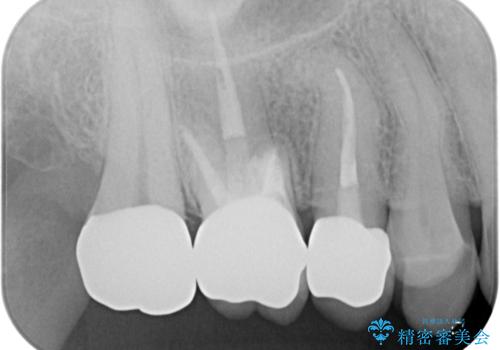

大臼歯では、根管治療後にも痛みが残ってしまったため、外科的歯内療法(歯根端切除術)を適用しました。外科処置直後は腫れや痛みなどがありましたが、半年が経過し、痛みがなくなり、レントゲン写真上でも炎症の消退が認められました。